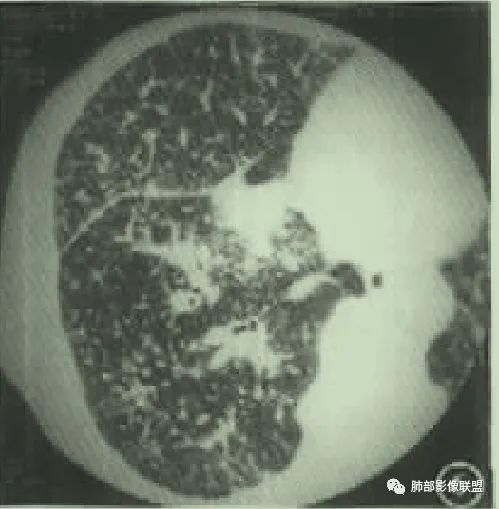

肺淋巴瘤表现多种多样。可表现为多发小结节!

有时表现为渗出性病变、肿块!

或实变+结节!